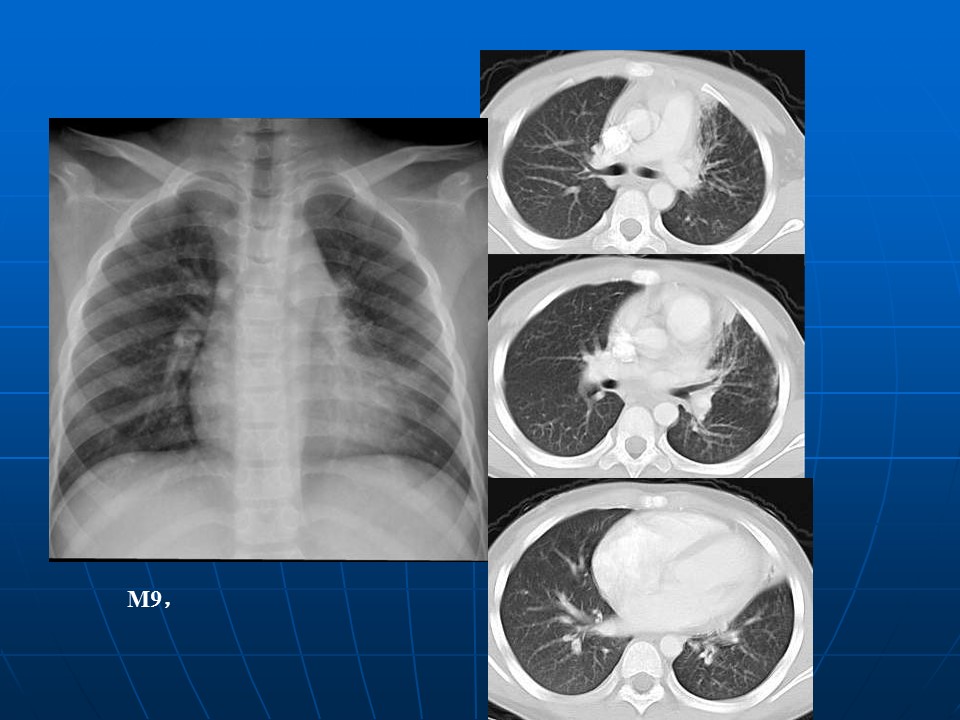

【病例】矽肺1例CT影像表现